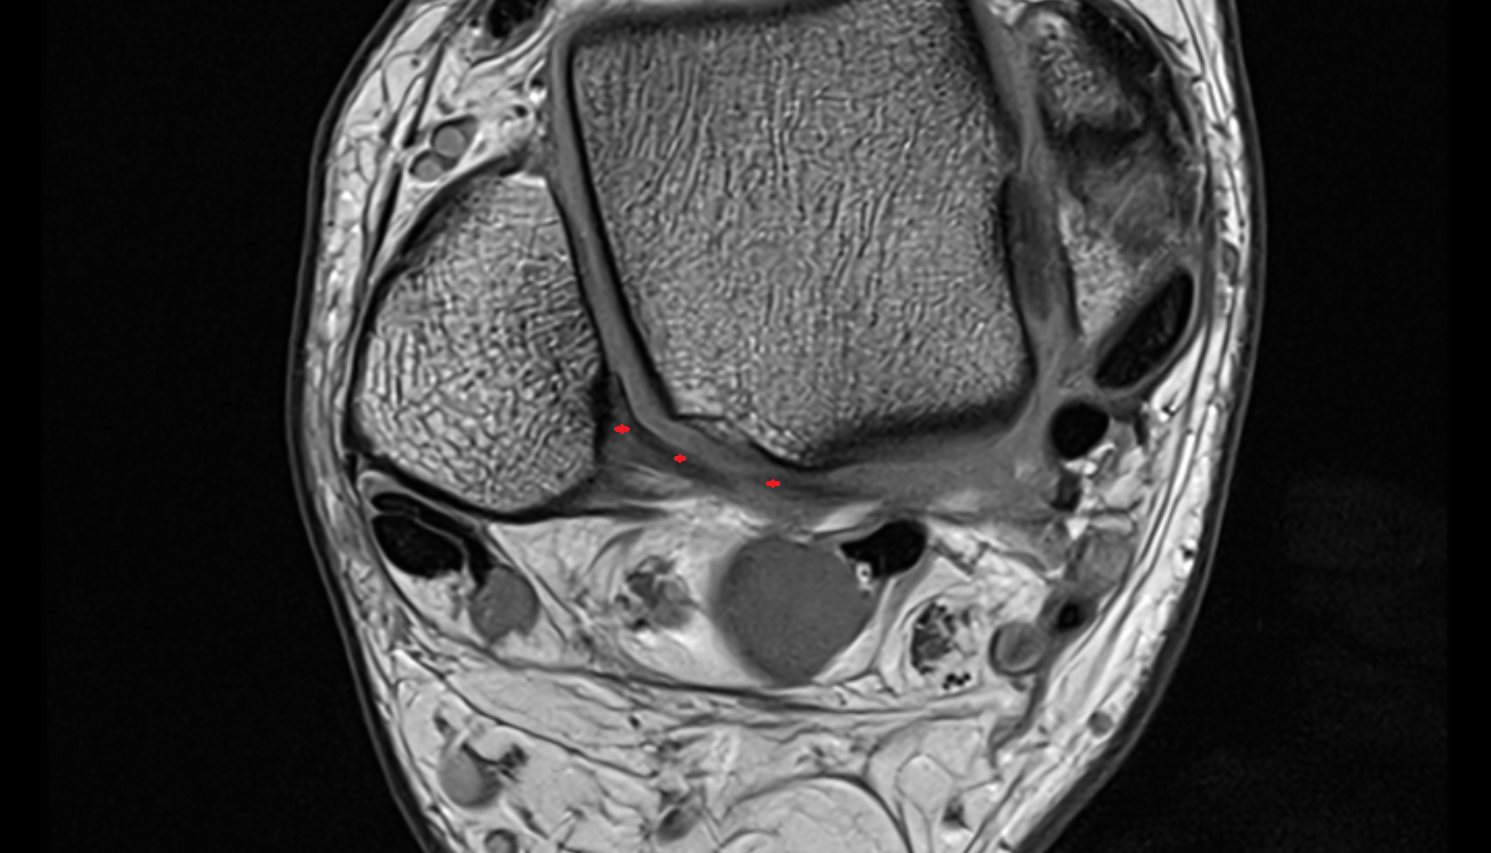

- Temporomandibular joint

- Mandibular condyle

- Mandibular fossa

- Articular disc of temporomandibular joint

- Articular eminence

- Superior head of lateral pterygoid muscle

- Inferior head of lateral pterygoid muscle